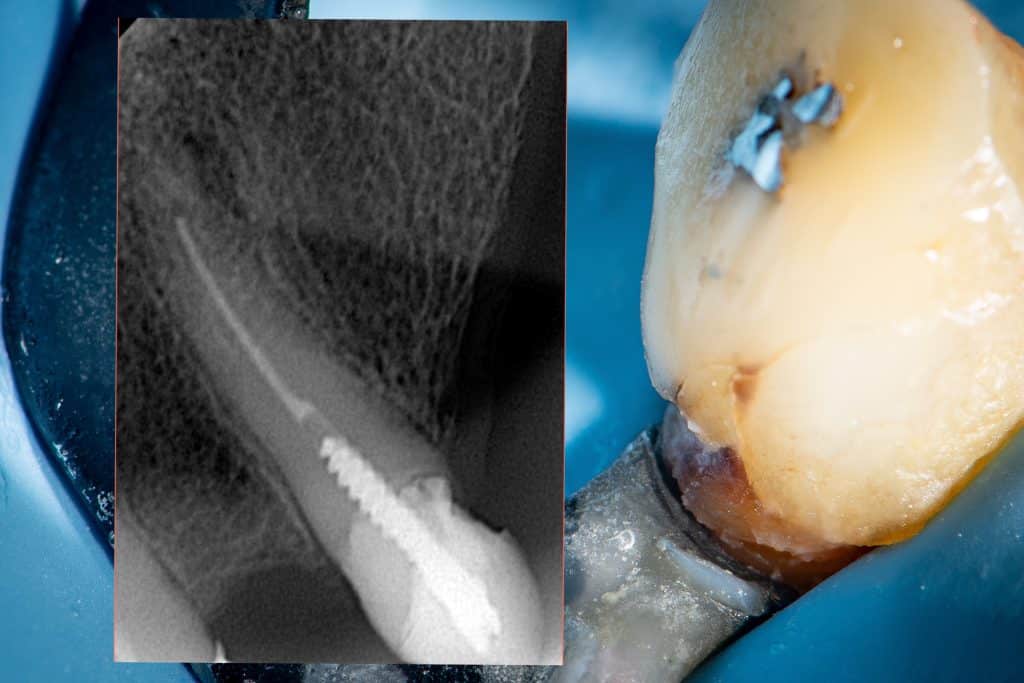

Tooth no23 with more than 14 years old filling.this type of treatment was good at its time and circumstances .Today, it is preferable to choose a treatment that reduces the risk of catastrophic failure and preserves the tooth structure for future interventions if anything goes wrong , as this will prolong the TOOTH’s longevity.